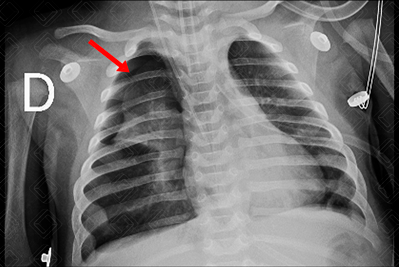

Descrição da figura 5: Radiografia de tórax AP no leito. Lactente, com 3 meses de vida, apresentando pneumotórax direito com atelectasia do lobo superior em correspondência (seta vermelha).